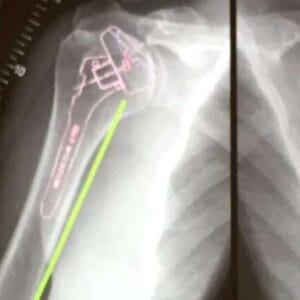

Greater Tuberosity Fractures

Patient information ShoulderThe greater tuberosity is the prominent area of bone at the top of the humerus and is the attachment for the two large, powerful rotator cuff muscles – supraspinatus and infraspinatus. It is injured/fractured in a fall by either landing directly onto the side of your shoulder or landing with